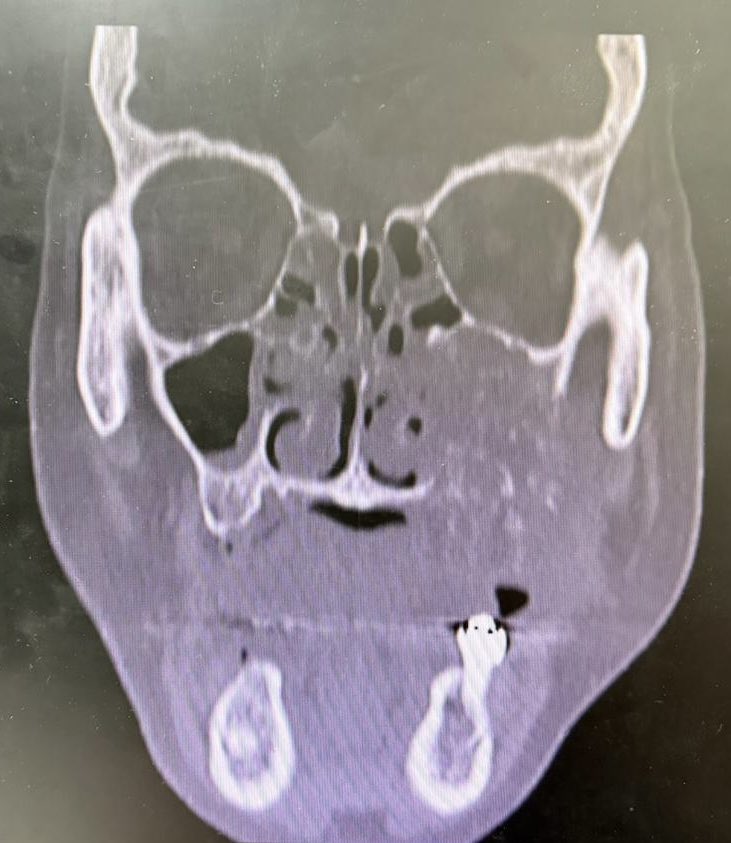

59-year-old woman with a destructive sinonasal tumor. Liver and iliac mets on CT. Biopsy performed (more pics below). Diagnostic opinions are welcome! #pathology #PathTwitter #surgicalpath #oralpath #entpath